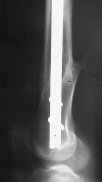

I presented a series of ~25 such cases at EuroTrauma'2004. Many cases were discussed here. I attach am example. Look also recent cases at http://www.hwbf.org/hwb/conf/alex58/scfx.htm,

I do realize that you are master surgeon, and congratulations on another excellent, spectacular case (result), but,

- Your last posted case: how is possible to have secure fixation with applied construct without additional casting, bracing or Ilizarov?

THX, initial images are

1,

2.

At that moment we had in stock only the 10 mm solid nails so of course there was no idea about early weight bearing. But it was quite enough for early knee ROM excersises (see attached). Two locking screws through the distal block provided that.